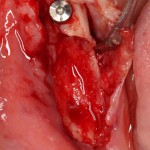

Что же касается нерезорбируемых мембран… Было дело, работал с Gore-Tex (дорого, очень дорого), титановыми сетками (заколебался потом доставать) и тефлоновыми Cytoplast:

результат:

или

с трудом выковыриваем сетку и ищем имплантат:

чтобы поставить формирователь: